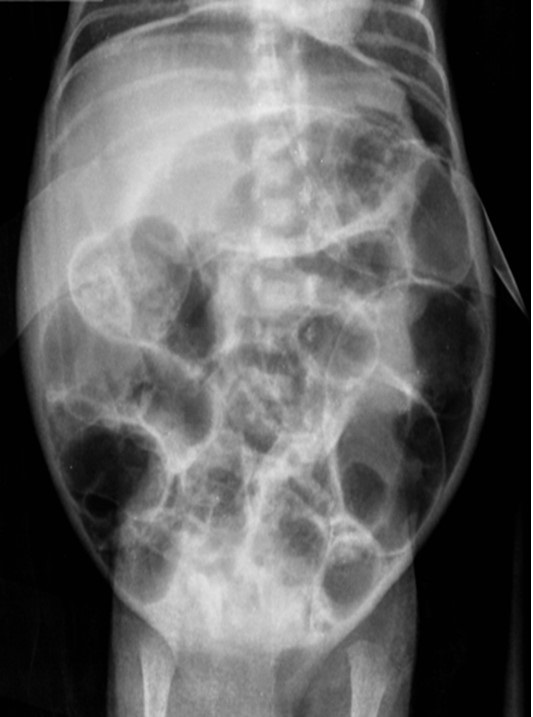

At 30 days of life, the baby developed an ill appearance, dark brown secretions from the orogastric tube, abdominal distension, increased abdominal girth, and a tender abdomen. Laboratory investigations showed raised white blood cell (WBC) counts of 12.8 x 103/L, C - reactive protein (CRP) 8.1 mg/L, Procalcitonin (PCT) 14ng/ml, and blood culture Staphylococcus haemolyticus. An abdominal x-ray revealed pneumoperitoneum (Fig. 1). Laparotomy showed a 0.5 cm perforation on the anterior aspect of the first part of the duodenum (Fig. 2) covered by fibrinous tissue and adhered to the inferior surface of the liver. Primary closure of the perforation was performed using 5-0 poliglecaprone and a Penrose drain was placed. Orogastric and orojejunal tubes were placed. On the third postoperative day (POD), the drain was removed followed by extubation. On POD-5, trophic enteral feeds were started via orojejunal tube and increased as per acceptance. At POD-15, the baby developed severe respiratory insufficiency which caused cardiac arrest and warranted intubation with advanced CPR but the baby succumbed.

Figure 2

Intraoperative picture showing 0.5 cm perforation at the first segment of anterior wall of duodenum (Yellow arrow). Blue arrow showing fibrin adhered to the inferior side of the liver.